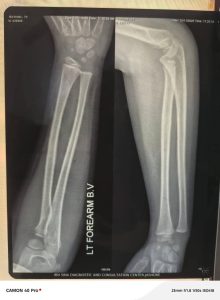

প্রধান শিক্ষক সাইফুল ইসলাম ঘটনাটি জানার সঙ্গে সঙ্গে রাইয়ানকে হাসপাতালে পাঠান এবং পরিবারের সঙ্গে যোগাযোগ করেন। চিকিৎসক প্রথমে হাতের কনুইয়ে চোটের আশঙ্কায় প্লাস্টার দিলেও পরবর্তী পরীক্ষায় নিশ্চিত হয়—তার হাতে কোনো ভাঙন বা ফ্র্যাকচার হয়নি।